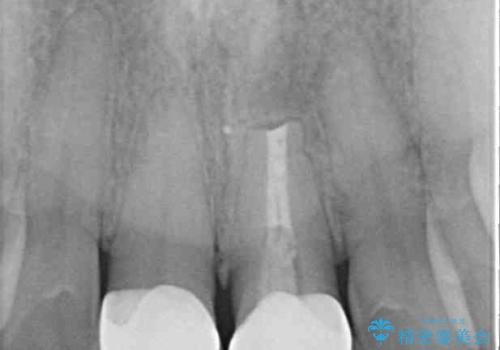

繰り返す痛み 下顎小臼歯の再根管治療